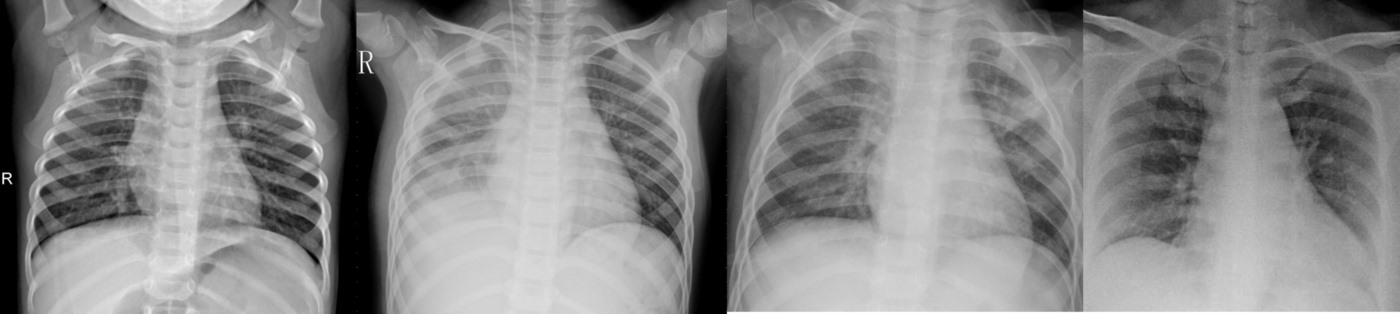

Nel 2020 il CRS4 ha partecipato al progetto DIMASDIA-COVID19. Una delle attività ha riguardato la diagnosi COVID19 per mezzo dell’analisi delle radiografie polmonari. Per mezzo del deep learning (intelligenza artificiale) si sono potute classificare con buona accuratezza le radiografie polmonari, distinguendo tra polmoniti batteriche, polmoniti virali non-covid e polmoniti covid.

Il sistema è stato sviluppato insieme a Neosperience S.p.A., Mikamai S.r.l., Looptribe srl , in collaborazione con l’Ospedale Sacco di Milano e l’Istituto Auxologico Italiano, , e finanziato dalla Regione Lombardia, dal Fondo Europeo per lo Sviluppo Regionale e dall’Istituto Veronesi.